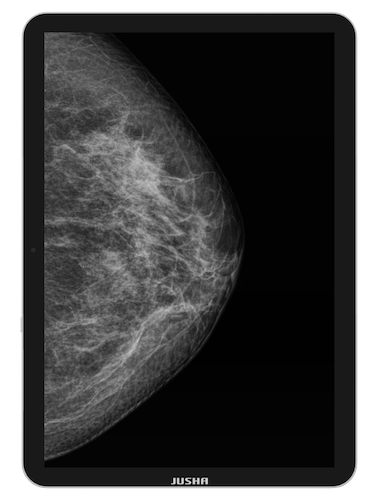

Objevte práci s monitorem, který je větší než obyčejné tablety |

Pro ovládání a navigaci na dotykovém displeji velikosti 13,5" můžete použít své prsty, myš i klávesnici |

CP620G – to není jen další monitor

Je to 13,5" přenosný medicínský diagnostický monitor, navržený k zobrazování a analýze dat formátu DICOM, navíc doplněný o nezbytné funkce jako jsou: